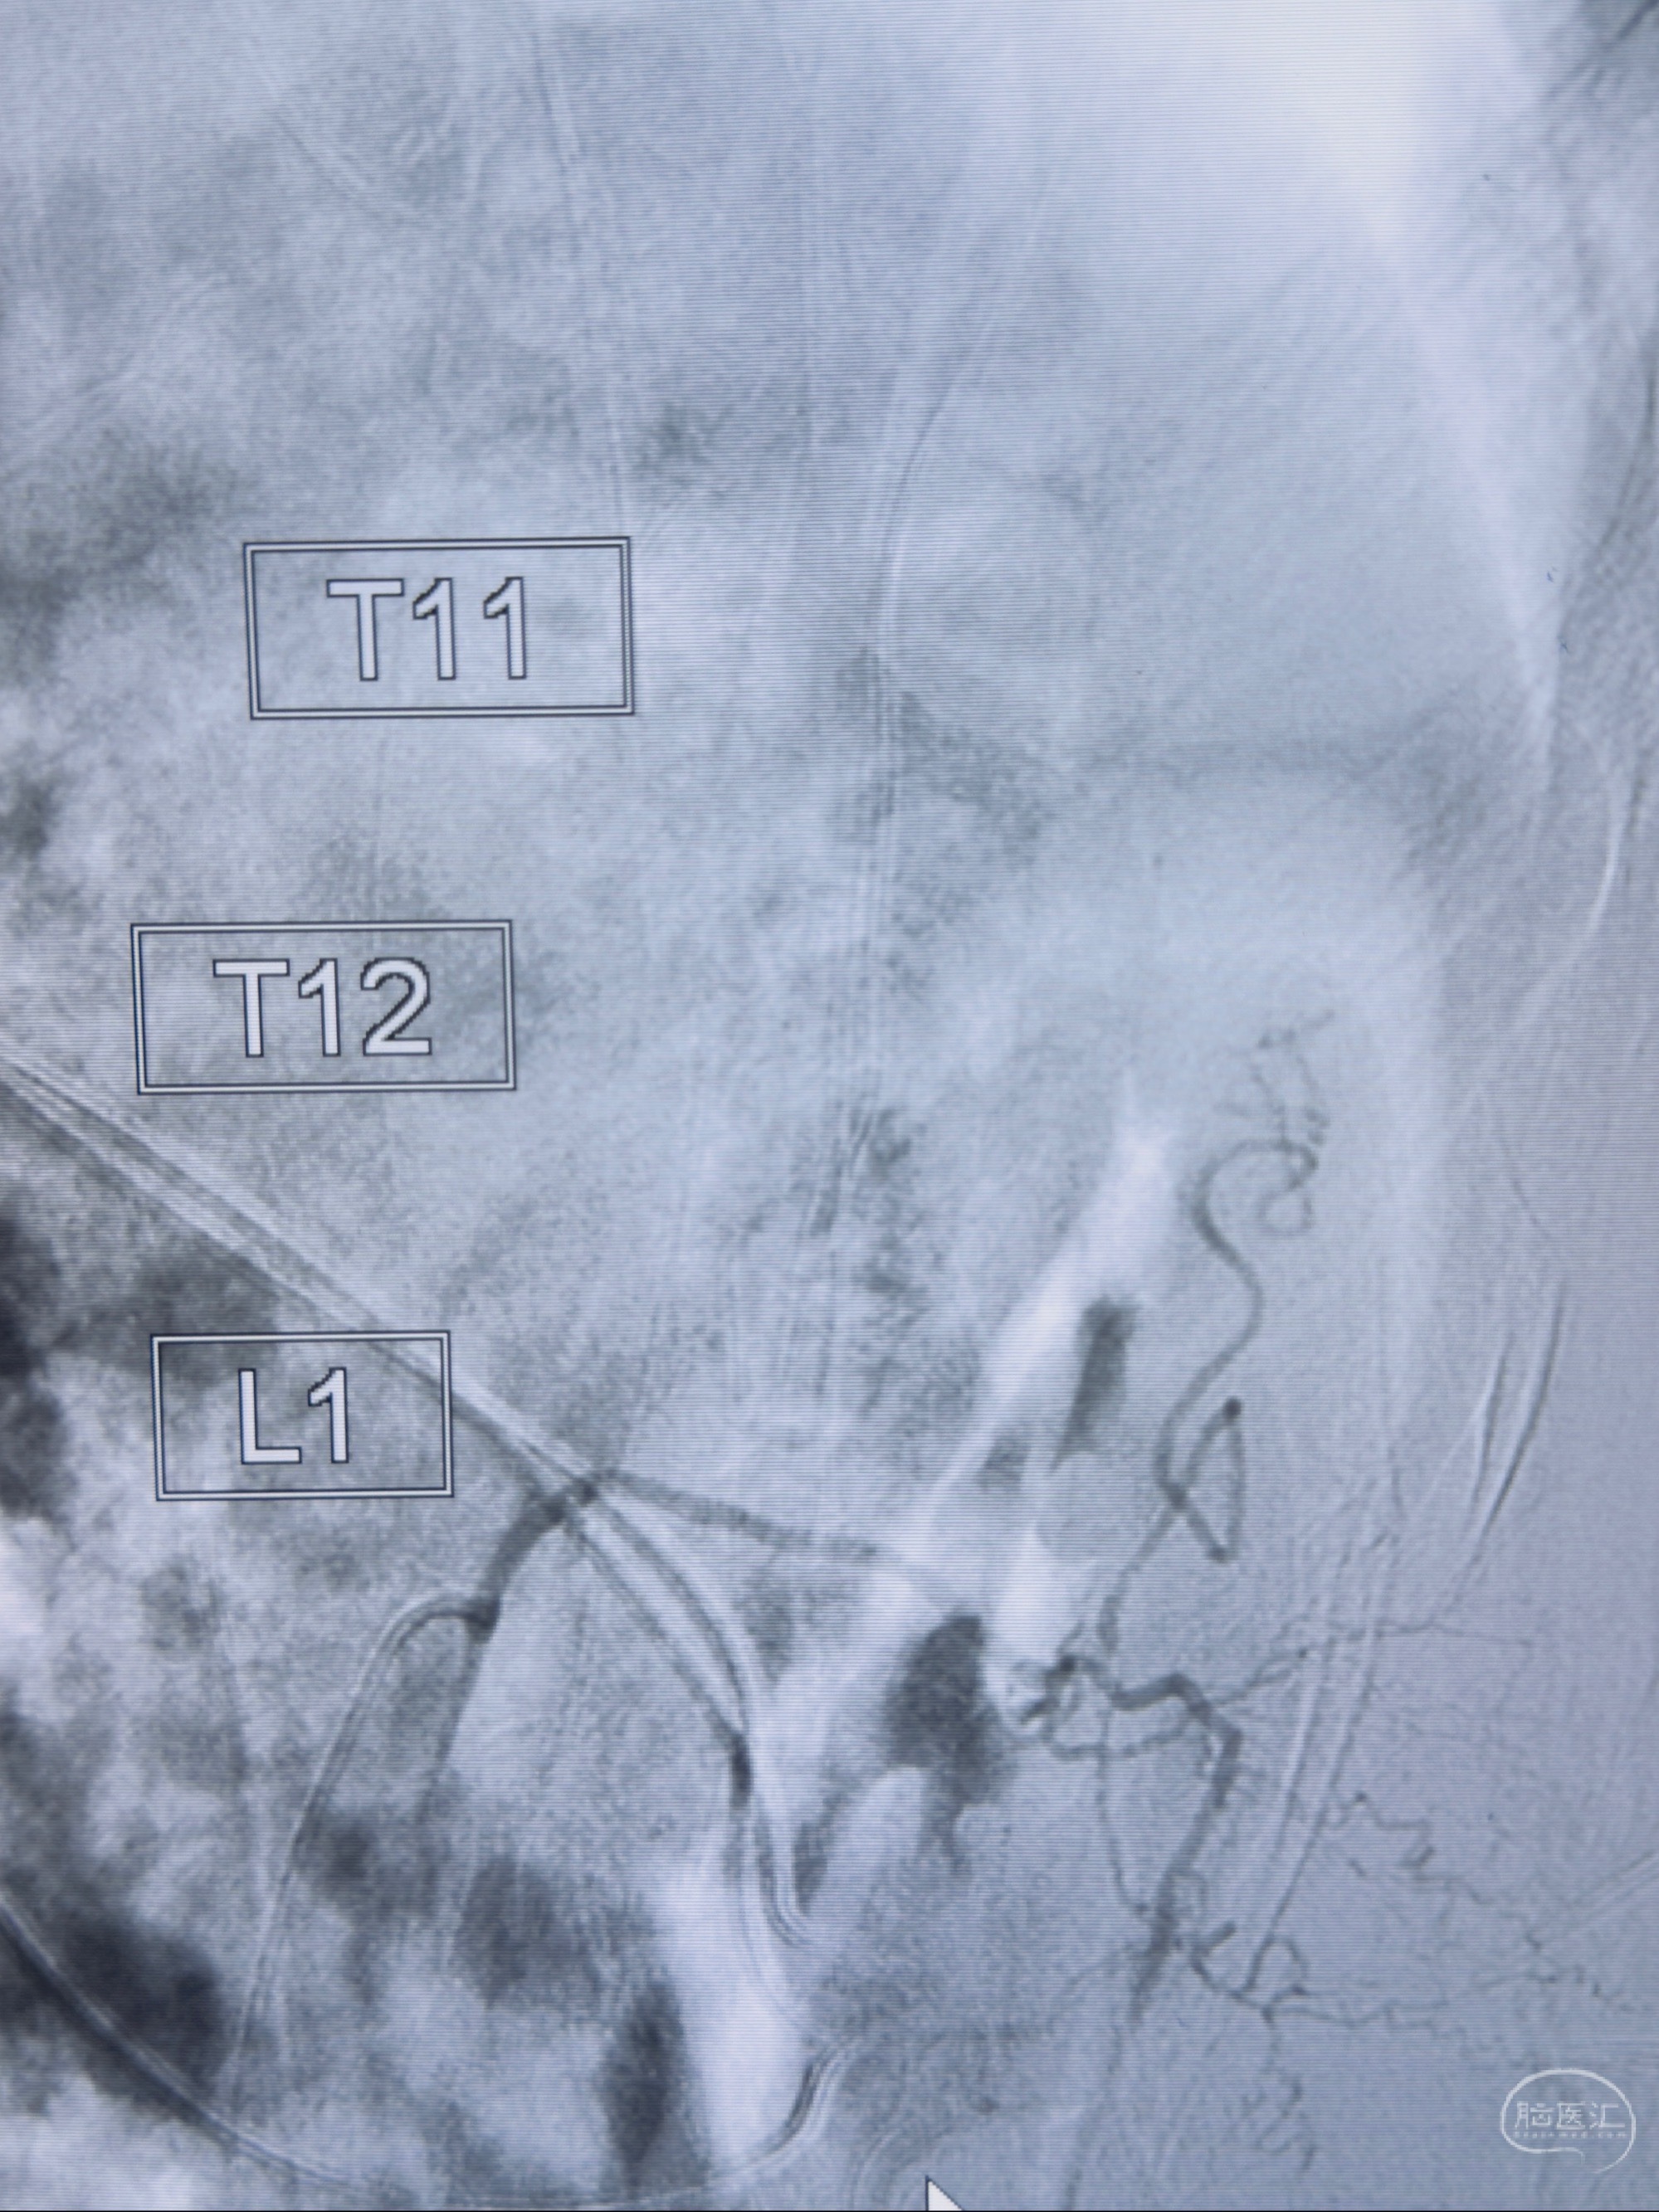

2023-10-13DSA:右侧L1水平硬脊膜动静脉瘘,供血动脉为右侧L1,附近动脉未见明确吻合供血,供血动脉处可见脊髓前动脉发出